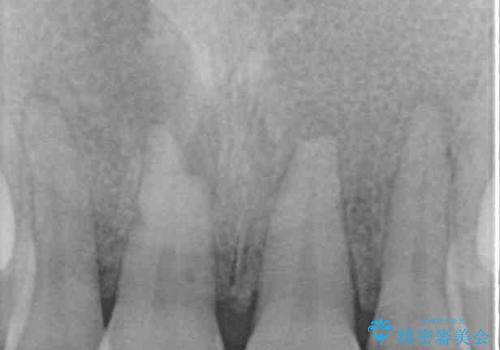

損傷がひどく、前歯4本と広範囲であったため、症状やレントゲン写真、検査結果が一致せず、定期的に経過を見ながら診断していくこととしました。

右側前歯は歯根が短くなり、パンチング状に歯根に透過像が認められたため、予後不良と判断し抜歯することとしました。

当初のレントゲン写真では根尖部に骨透過像が認められた両サイドの2歯は、歯髄の正常な反応が認められたためそのまま保存し、左側前歯は歯髄が失活していたため根管治療を行うこととしました。

事故直後のレントゲン写真では全ての歯の根尖部に骨透過像が認められましたが、治療後には全ての透過像がなくなっていました。